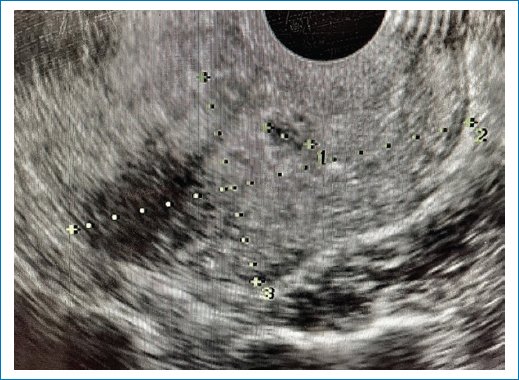

Paciente de 38 años, gestas 3, cesáreas 2, que acudió al hospital por sangrado transvaginal, con ultrasonido que reportaba saco gestacional de 21 mm, embrión de 6.6 semanas por longitud cráneo-cauda, localizado en la pared anterior del istmo uterino, sugiriendo inserción en cicatriz uterina (Fig. 1). La cuantificación de la subunidad beta de la gonadotropina coriónica humana (hCG-β) se encontraba en 6,402 mUI. Se ofertó tratamiento médico o quirúrgico, explicando los posibles riesgos y complicaciones, y se optó por manejo conservador. Una vez corroborados los valores normales de las pruebas de función hepática se realizó el procedimiento en quirófano, bajo anestesia regional, en posición de litotomía. Se colocó un espejo vaginal y se realizó una punción del saco gestacional transcervical con aguja Echotip de Cook de 22 G y 15 cm, guiada por ultrasonido endovaginal, administrando metotrexato 1 mg/kg intrasacular, y luego una dosis única intravenosa de 50 mg, sin complicaciones. La paciente fue egresada a las 24 horas posterior al procedimiento.

Figura 1. Embarazo en cicatriz uterina de cesárea previa. Embrión de 6.6 semanas por longitud cráneo-cauda.